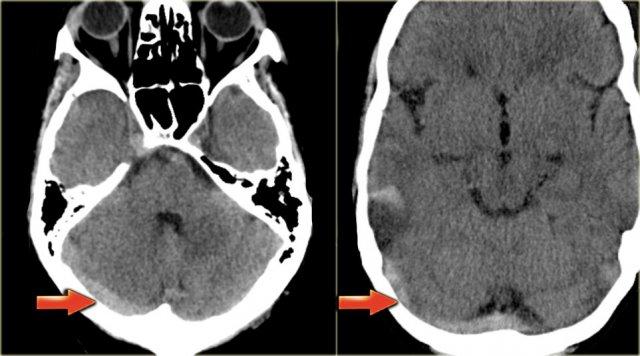

Το δικαστήριο αναγνώρισε αποζημιωτική ευθύνη του Ελληνικού Δημοσίου για τον θάνατο γυναίκας που επήλθε συνεπεία θρομβωτικού επεισοδίου, το οποίο συνδέθηκε αιτιωδώς με τη χορήγηση του εμβολίου της AstraZeneca.

Συγκεκριμένα, ελήφθη υπόψη η στενή χρονική εγγύτητα μεταξύ της χορήγησης του εμβολίου και της εκδήλωσης του επεισοδίου, η απουσία εναλλακτικών παραγόντων κινδύνου

στο ιατρικό ιστορικό της θανoύσας, καθώς και η τεκμηρίωση από τη διεθνή

επιστημονική βιβλιογραφία που αναγνωρίζει τη συγκεκριμένη σπάνια παρενέργεια.